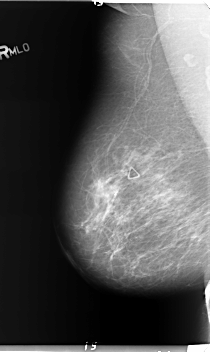

B_3152_1.RIGHT_MLO

RIGHT_MLO LINES 5976 PIXELS_PER_LINE 3560 BITS_PER_PIXEL 12 RESOLUTION 50 NON_OVERLAY

FILE: B_3152_1.LEFT_CC.OVERLAY

TOTAL_ABNORMALITIES 1

ABNORMALITY 1

LESION_TYPE MASS SHAPE LOBULATED MARGINS CIRCUMSCRIBED-ILL_DEFINED

ASSESSMENT 4

SUBTLETY 4

PATHOLOGY BENIGN

TOTAL_OUTLINES 1

BOUNDARY